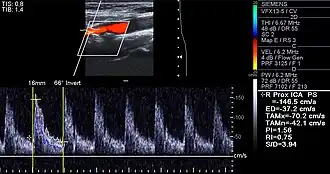

Examples of anatomical detection methods include coronary calcium scoring by CT, carotid IMT (intimal media thickness) measurement by ultrasound, and intravascular imaging techniques, such as intravascular ultrasound (IVUS), and intravascular optical coherence tomography (OCT),[85][86] allowing direct visualization of atherosclerotic plaques.